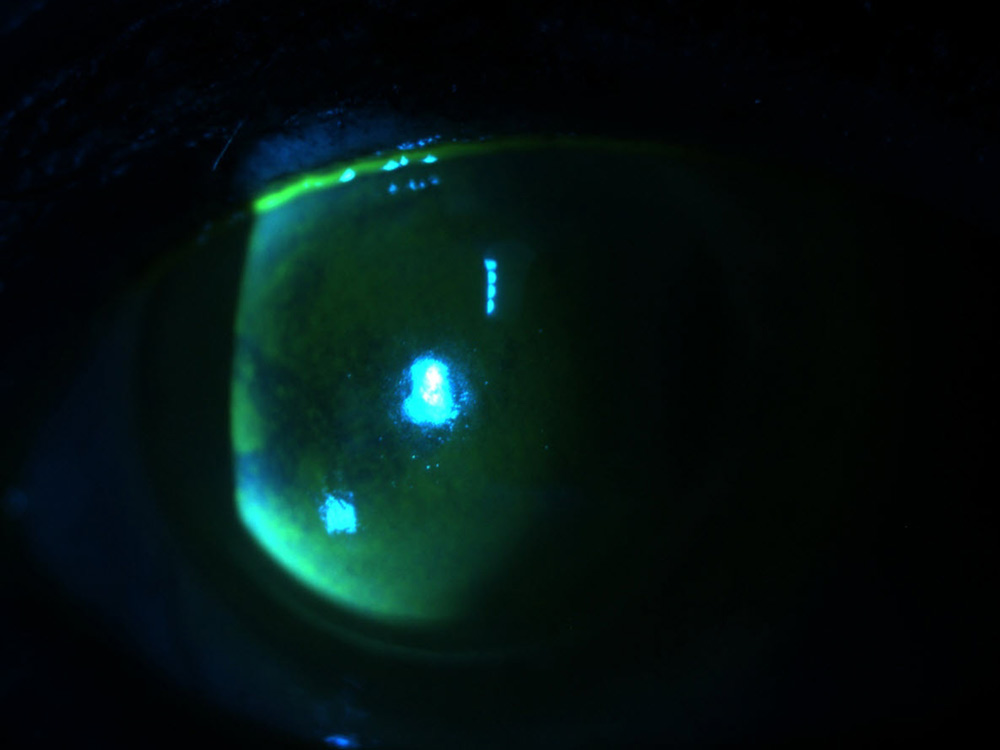

Source: Kavitha Sivaraman, MD